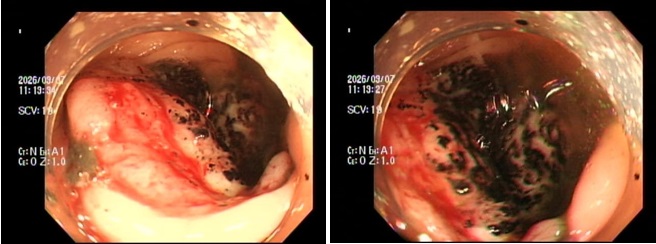

Hình ảnh qua ngã nội soi đại trực tràng. (Ảnh: BVCC)

Trường hợp đầu tiên là P.V.P.U (sinh năm 1991) đến khám chỉ vì... ông xã thấy dạo này da dẻ quá xanh xao. Bản thân U thỉnh thoảng cũng cảm thấy đau bụng nhẹ, thoáng qua nhưng lại tặc lưỡi bỏ qua vì nghĩ là rối loạn tiêu hóa thông thường. Khi thăm khám, bác sĩ phát hiện chị bị thiếu máu nặng. Ngay lập tức, chị được chỉ định nội soi đại tràng, kết quả khiến cả hai vợ chồng sững sờ: Có một khối u lớn ở đại tràng phải, bề mặt loét và rất dễ chảy máu, kết quả mô học khẳng định: Ung thư đại trực tràng.

Trường hợp thứ 2 là anh N.H.H.H (sinh năm 1995) đến viện với dáng vẻ mệt mỏi rã rời, than phiền hay bị chóng mặt kèm theo rối loạn đi cầu. Cứ nghĩ do làm việc quá sức, nhưng kết quả xét nghiệm lại báo động tình trạng thiếu máu nặng. Bác sĩ cho tiến hành nội soi đại trực tràng và phát hiện một khối u dạng vòng nhẫn đang chảy máu rỉ rả ở vùng trực tràng. Giải phẫu bệnh một lần nữa gọi tên: Ung thư trực tràng.